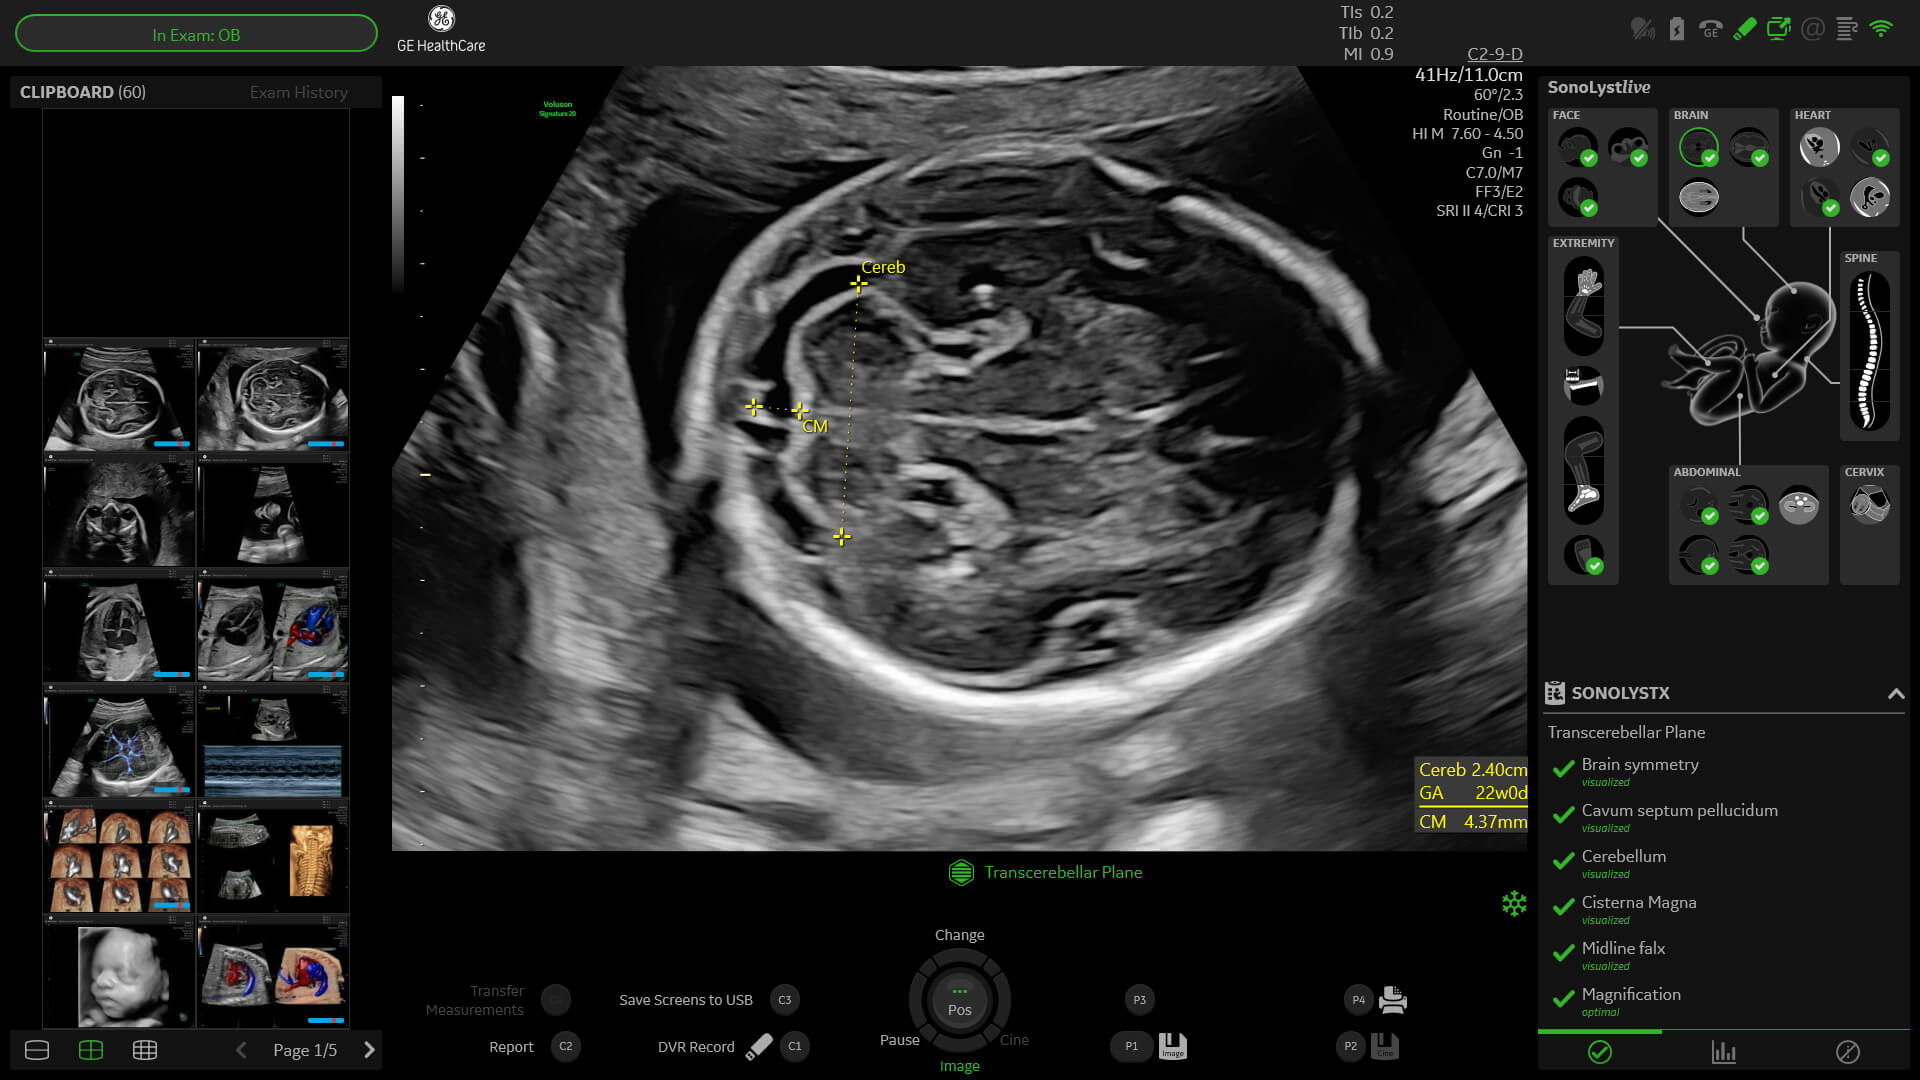

SonoLyst

SonoLyst* reduces the time to complete the standard ISUOG 2nd trimester exam requirements by 40%. And with SonoLyst live, it means no more stopping to freeze, annotate, or store.